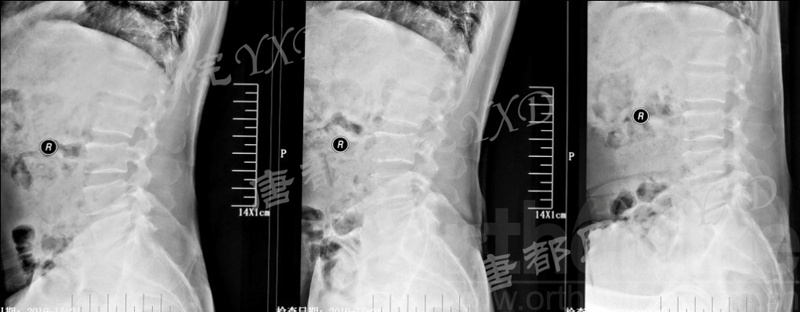

影像学检查:

诊断:腰椎椎间融合术后融合器后移

手术方案:显微镜辅助MI-TLIF腰椎翻修术

术中视频:http://api.orthonline.com.cn/attach/Case3.mp4(术中发现因前次手术全椎板及关节突切除,TLIF的第一步,即关节突关节的定位落脚点难以找到。显微镜下通过Kambin三角解剖位置,进行从外至内的解剖,寻找cage尾端;此外,因大量瘢痕渗血,难以进行充分止血;但在显微镜的照明和放大视野下,操作均可在不伤及神经的前提下进行。由于终板骨质吸收,椎间隙塌陷,导致术野内可同时看到出行根和走行根。而在显微镜下,能够通过调整景深和视线角度,精准充分处理椎间隙骨性终板。无手术并发症)

术后疗效:VAS左下肢1分、腰1分;左侧直腿抬高试验、加强试验阴性。